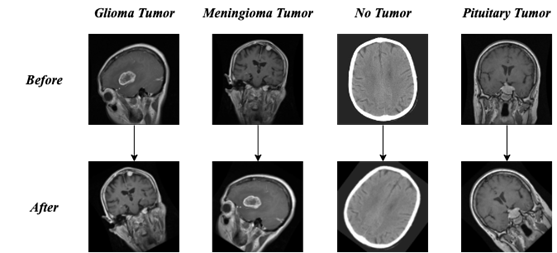

2.2.1 Geometric transformation method

Geometric transformation is the geometric transformation of the image, including flip, rotate, scale and other types of operations, which can enrich the position and scale of the objects appearing in the image, so as to satisfy the translation invariance and scale invariance of the model. We use to rotate the image randomly between (-45,45) degrees and change the brightness of the image randomly to (0.8, 2.0) of the brightness of the original image, the specific transformation effect is shown in Fig 3.